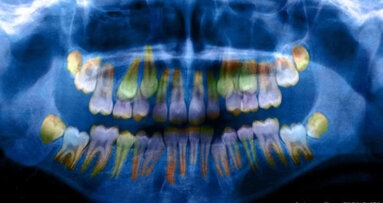

ALS je stav, který se obvykle projevuje kolem padesátého nebo šedesátého roku života. Jeho příčina není známa a neexistuje žádný test, který by předpovídal jeho nástup. Ani genetické studie doposud nebyly schopny odhalit mnoho informací, a ačkoli se odborníci domnívají, že při vývoji onemocnění hrají významnou roli faktory životního prostředí, neexistují jasné náznaky toho, které z nich to jsou. Nyní vědci ve své studii použili lasery k mapování růstových prstenců, které se denně vytvářejí na zubech, a objevili, že u pacientů s ALS se ukládají metabolizované kovy jinak, než u pacientů bez tohoto onemocnění.

Studie odhalila u 36 pacientů s ALS, ve srovnání s 31 kontrolními, narušení regulace příjmu směsi základních prvků, včetně zinku a mědi, jakož i toxinů jako je olovo a cín. Markery narušení regulace příjmu kovů byly pozorovány také u zubů myší s ALS, které ve srovnání s kontrolní skupinou také vykazovaly rozdíly v rozložení kovů v mozku.